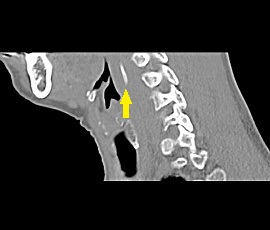

[咽頭腔外魚骨異物] 手術:内視鏡的粘膜下層剥離術(異物除去)

CT画像